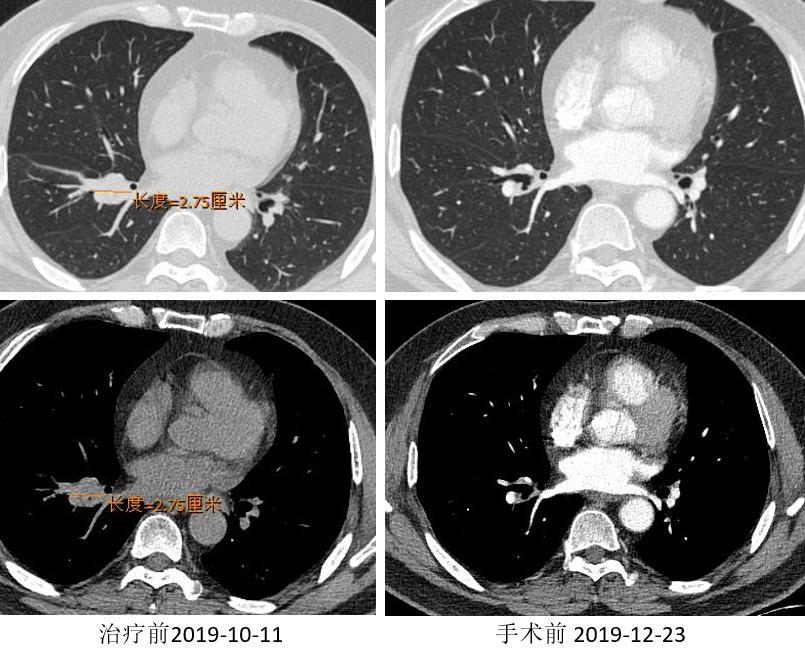

胸部CT

外周淋巴结CT

两周期“信迪利+AP”免疫治疗联合化疗方案。

2019.12.10 行“右肺上叶切除术”。

术后病理:(右上叶)浸润性腺癌(腺管型95%,微乳头型5%),(纵隔4R组淋巴结)阴性。病灶内浸润性腺癌(约占20%),见较多区域纤维化伴组织细胞、淋巴细胞浸润,另见胆固醇结晶、多核巨细胞及肉芽肿反应,符合化疗后反应。